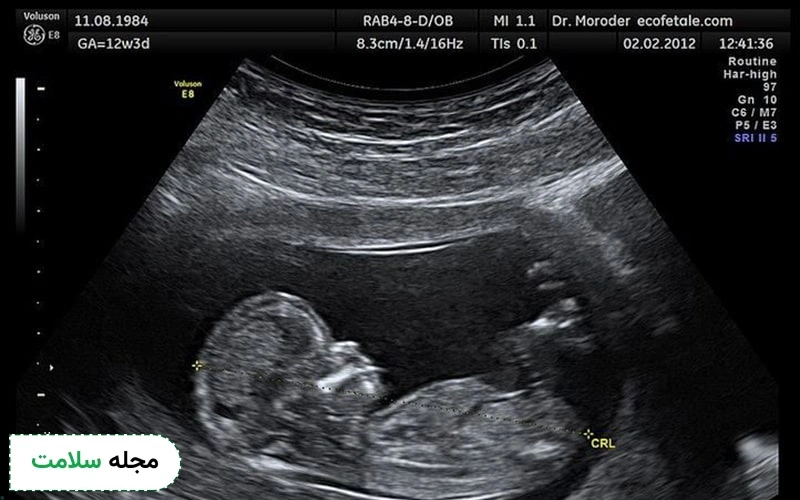

در سونوگرافی بارداری، اکوژنیک بودن برخی ساختارها مانند استخوانهای جنین یا جفت میتواند نشاندهنده سلامت طبیعی آنها باشد.

اکوژن در سونوگرافی بارداری

اکوژن در سونوگرافی بارداری به نواحی گفته میشود که امواج صوتی را بیشتر بازتاب میدهند و در تصویر روشنتر دیده میشوند. این نواحی میتوانند در جنین یا جفت دیده شوند و معمولاً نشاندهنده بافتهای متراکمتر یا ساختارهای خاص هستند. ممکن است پزشک در سونوگرافی بارداری متوجه نواحی اکوژن غیرطبیعی در بدن جنین شود که به شرح زیر هستند: